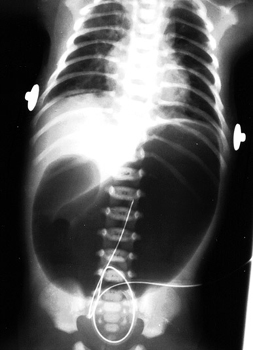

Pediatric Radiology > Abdominal > Neonatal > Duodenal Atresia (2)

Duodenal Atresia - Radiographic Features

The most prominent feature is the "double bubble" sign (dilated stomach and duodenal bulb) -- dilated stomach and no gas distal to the proximal duodenum. Stated another way, there is no gas in the rest of the small or large bowel. |